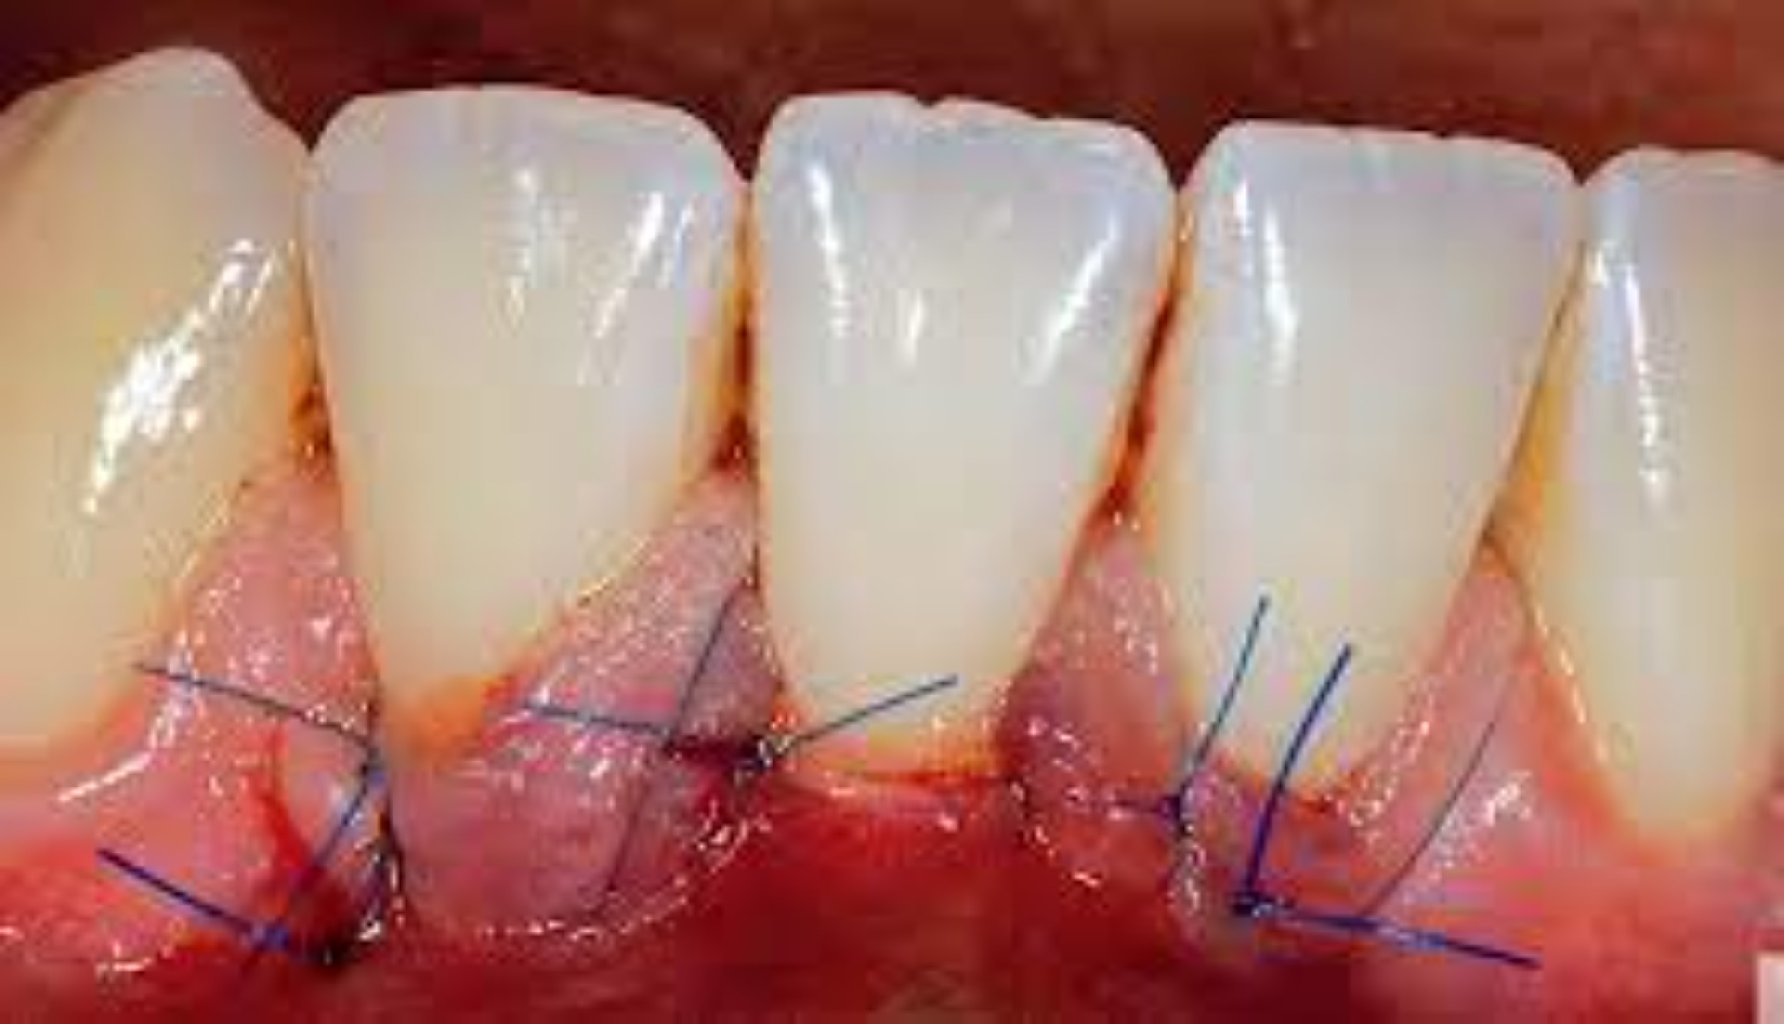

Estetik Diş əti Səviyyələndirilməsi Prosedurları: Gingivektomiya: Bu, artıq diş əti toxumasının ç ...